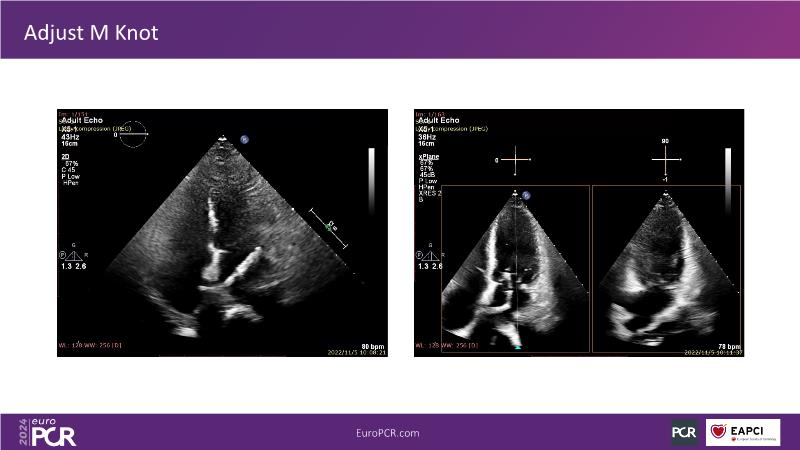

Watch this session to gain insights into the clinical evidence of mitral TEER therapy for the Asian population, learn techniques for implanting a MitraClip in patients with challenging anatomy, and understand how to use the four clip sizes for optimal outcomes. The session also covers educational aspects of clipping in dextrocardia, the benefits of reserve bending of the transseptal needle for tenting and puncture, new steering maneuvers for dextrocardia patients, and the importance of understanding anatomy and collaborating closely with the echo team for success.